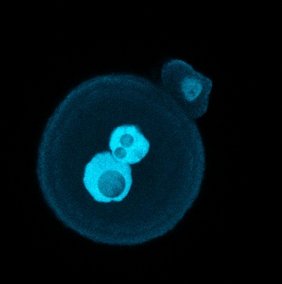

Neben der genomischen Prägung, bei der einzelne Gene ausgeschaltet werden, gibt es ein weiteres Phänomen, das die Forscherinnen und Forscher untersuchten. Bei weiblichen Zellen, die im Gegensatz zu männlichen zwei X-Chromosomen besitzen, wird eines davon sehr früh in der Entwicklung völlig stummgeschaltet. Das ist bei fast allen Säugetieren der Fall, auch beim Menschen.

„Wir haben herausgefunden, dass das Enzym PRC2 dabei eine entscheidende Rolle spielt“, sagt Andergassen. „Wenn wir dieses Enzym entfernen, wird das stumme X-Chromosom wieder aktiviert.“ Das Ergebnis dieser Forschung könnte für X-chromosomale Erkrankungen von Bedeutung sein, da die Reaktivierung des stummen gesunden Gens die Fehlfunktion des aktiven Gens ausgleichen könnte.